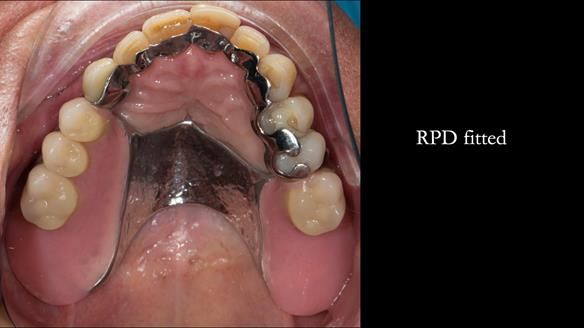

Instead, we made a Scandinavian-style, metal-based lower RPD.

A metal-based upper RPD was made,

with metal backings incorporated to future-proof the design

should further teeth fail.